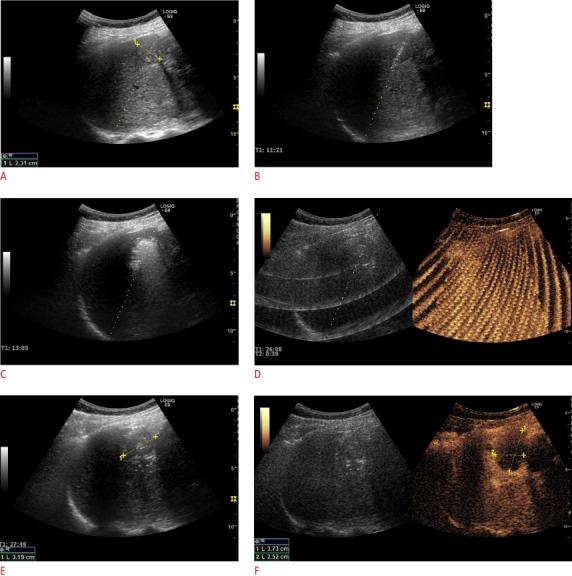

Ablation is a valuable treatment alternative to surgery for colorectal liver metastases. This study reports the long-term clinical outcomes in patients treated with ablation for colorectal liver metastases with or without extrahepatic metastases.

Patients with colorectal liver metastases treated with ultrasound-guided ablation at Herlev Hospital, Denmark were included in this retrospective study.

This study included 284 patients with 582 metastases. Complete ablation was obtained in 258 patients (91%) evaluated within 6 weeks. During follow-up, 94 patients (33%) developed local recurrence. The median survival for all patients was 31 months, with 1-, 3-, and 5-year survival rates of 82%, 45%, and 21%, respectively. The median survival for patients with extrahepatic metastases (n=49, 17%) was 24 months compared with 33 months for patients without (P=0.142). Propensity score-adjusted Cox regression showed that extrahepatic metastases were associated with increased mortality, with a hazard ratio (HR) of 1.45 (95% confidence interval [CI], 1.02 to 2.05; P=0.039). In multivariate Cox regression analysis for all patients, increased mortality risk was found for a diameter ≥2.6 cm (HR, 1.59; 95% CI, 1.23 to 2.05), >1 metastasis (HR, 1.66; 95% CI, 1.28 to 2.16), and extrahepatic metastases (HR, 1.45; 95% CI, 1.04 to 2.03). Male sex (HR, 0.75; 95% CI, 0.58 to 0.98) and receiving chemotherapy (HR, 0.69; 95% CI, 0.52 to 0.92) were associated with decreased mortality.

对于结直肠癌肝转移患者,消融术是一种有价值的手术替代治疗方法。本研究报告了接受消融术治疗的有或无肝外转移的结直肠癌肝转移患者的长期临床结局。

本回顾性研究纳入了在丹麦赫勒夫医院接受超声引导下消融术治疗的结直肠癌肝转移患者。

本研究纳入了284例患者,共582处转移灶。在6周内评估的258例患者(91%)实现了完全消融。在随访期间,94例患者(33%)出现局部复发。所有患者的中位生存期为31个月,1年、3年和5年生存率分别为82%、45%和21%。有肝外转移的患者(n = 49,17%)中位生存期为24个月,无肝外转移的患者为33个月(P = 0.142)。倾向评分调整后的Cox回归显示,肝外转移与死亡率增加相关,风险比(HR)为1.45(95%置信区间[CI],1.02至2.05;P = 0.039)。在所有患者的多因素Cox回归分析中,发现直径≥2.6 cm(HR,1.59;95% CI,1.23至2.05)、转移灶>1个(HR,1.66;95% CI,1.28至2.16)和肝外转移(HR,1.45;95% CI,1.04至2.03)与死亡风险增加有关。男性(HR,0.75;95% CI,0.58至0.98)和接受化疗(HR,0.69;95% CI,0.52至0.92)与死亡率降低有关。